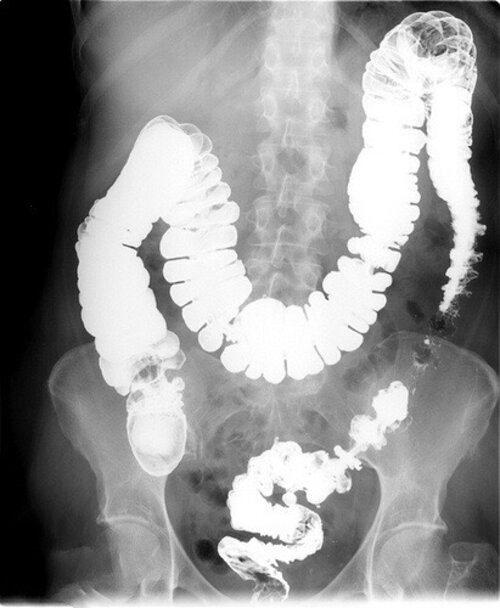

Вижте сканирането на органите на жена, която започнала с лош дъх, запек и киселини, а завършила с доклад от патологоанатом.

Рак на дебелото черво при жена, която се оплаквала от чест запек

Тази жена не предприела никакво лечение, а използвала случайни лекарства, които ѝ препоръчали в аптека с думите: „Това сега е добро за стомаха, пробвайте!“ Вероятно сте чували нещо подобно в аптеката във вашия квартал.